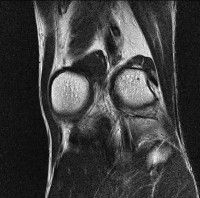

무릎 mri 간단히 봐주실 수 있으시나요 ㅠㅠ

안녕하세요 8년전 십자인대 수술하고 최근 무리한 운동에 무릎 불편감이 생겨서

mri 찍었습니다.

진단결과는 첫 찍은 병원에서 활액막염 이라는 진단을 받았습니다. 혹시 봐주실 수 있으실까요?

올라온 MRI가 단편적이라서 정확한 진단에 어려움이 있지만 십자인대에는 큰 이상이 있지는 않은것 같으며, 무릎관절내 물이 있는 것으로 보아 활액막염의 진단이 맞을 것 같습니다.

하지만 단편적인 영상이기 때문에 촬영병원에서 정확한 판독지 등을 받으시는 것이 좋겠습니다.